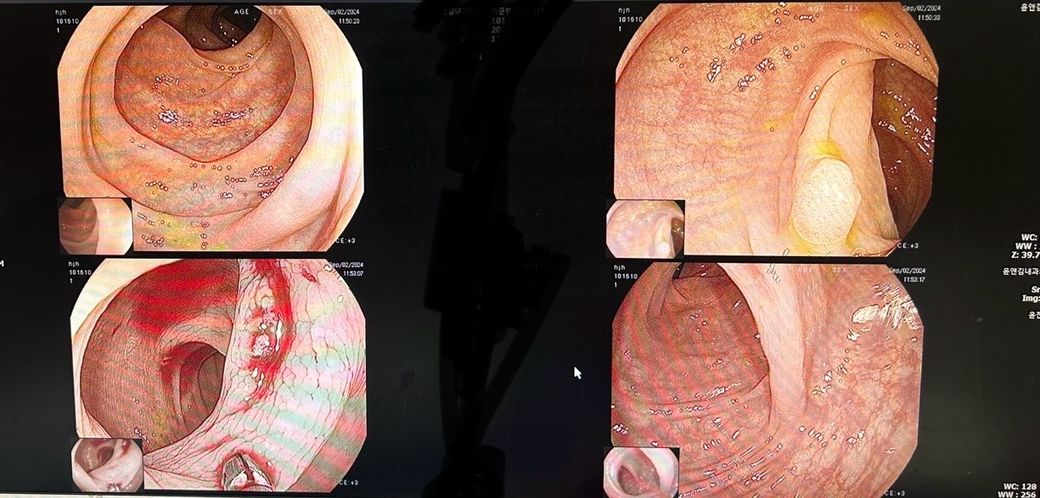

위내시경 한 사진입니다

대장내시경 한 사진입니다.

두곳다 용종이 나와서 …

암일수 있을까요?? 좀 걱정 되기도 하고..

올려주신 사진만으로는 알기 어렵고 내시경 판독지나 조직검사 결과 확인이 필요하겠습니다.

위 내시경 사진에서 혹처럼 보이는 부위의 변화가 있어 외부에서 위를 압박했을 가능성이 생각됩니다.

조직검사 결과에 따라 추가적으로 복부 CT 검사가 필요할 수 있겠습니다.